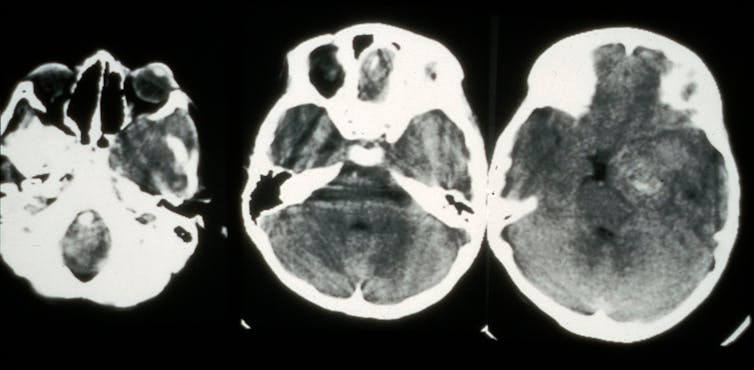

Our group has been developing new ways to identify disease in scans like MRI and CT, as well as digitized tissue slide images.

To identify the likelihood of a successful response before therapy begins, our lab is building software to examine routine diagnostic CT scans of lung tumors. The software looks at tumor texture, intensity and shape, as well as the shape of vessels feeding the nodules. This information might help oncologists optimize the therapy dosage or alter a patient’s treatment plan.